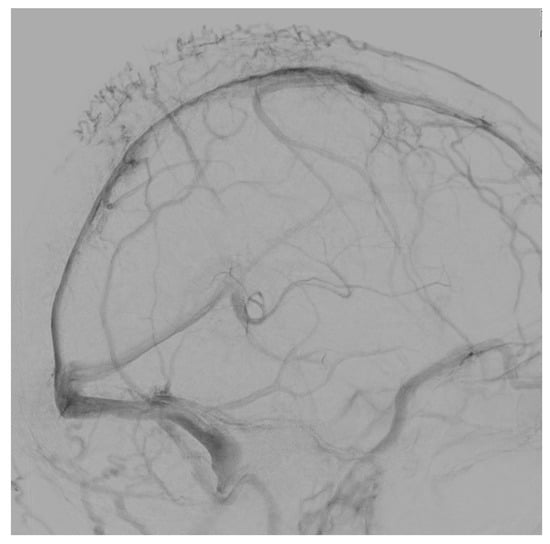

3.3.1. Case 1